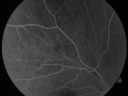

FLUORESCEIN ANGIOGRAPHY: FA shows hyperfluorescence in the areas of the chorioretinal scars. The neovascular complex has a minimal amount of leakage in the late frames in the right eye and there is fairly good perfusion in the periphery of both retinas out to the far periphery as far as the photographic field can show.